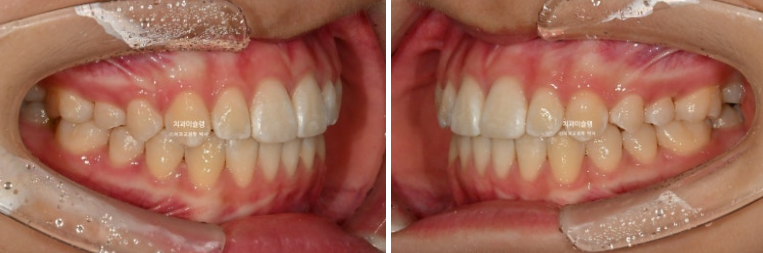

24.04~25.11

앞니 돌출과 높낮이 차이를 개선하고 약간의 치간삭제를 더해 치료했으므로 이제 더이상 앞니가 토끼이같이 커보이지 않습니다.

돌출 앞니와 입매 개선이 눈에 띕니다.